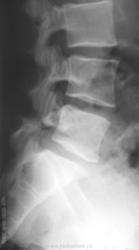

Пол пациента: Женский пол Тип патологии: Врожденная патология Область исследования: Скелетно-мышечная система Методы исследования: Rg Молодая женщина пришла на снимок поясничного отдела. Другая женщина, которая занимается рукопашным боем, обратилась с жалобами на боли в пояснице, после неудачного броска. https://radiomed.ru/sites/default/files/styles/case_slider_image/public/user/712/sl274202.jpg?itok=nrVgJub5 https://radiomed.ru/sites/default/files/styles/case_slider_image/public/user/712/sl274211.jpg?itok=ON6uvgKI https://radiomed.ru/sites/default/files/styles/case_slider_image/public/user/712/sl274212.jpg?itok=NmuMvaE1 https://radiomed.ru/sites/default/files/styles/case_slider_image/public/user/712/sl274213.jpg?itok=nP2dg6tE ID:18475 Пт, 27/01/2012 - 18:10 #1 Фаина Не на сайте Был на сайте: 2 года 11 месяцев назад Зарегистрирован: 14.12.2008 - 16:51 Публикации: 323 В первом случае, кроме остеохондроза и несросшихся апофизов, честно говоря, ничего критичного" не увидела. А во втором случае, не спондилолиз ли в L5?! Пт, 27/01/2012 - 18:17 #2 Наталия Не на сайте Был на сайте: 8 лет 7 месяцев назад Зарегистрирован: 30.07.2008 - 13:24 Публикации: 538 Во втором случае вероятнее спондилолиз. Пт, 27/01/2012 - 18:25 #3 Глазков Игорь А... Не на сайте Был на сайте: 9 месяцев 1 неделя назад Зарегистрирован: 19.12.2008 - 20:41 Публикации: 1597 Шморля в каудальной части тела позвонкаТ12 Прийди к Себе Пт, 27/01/2012 - 21:15 #4 И.Бондаренко Не на сайте Был на сайте: 3 дня 7 часов назад Зарегистрирован: 13.09.2011 - 22:55 Публикации: 9206 Случай №1. Грыжа Шморля Т12, несросшиеся апофизы L2,5 или обызвествившиеся грыжи дисков. Случай №2. Спондилолиз дужки L5. Ср, 01/02/2012 - 21:08 #5 Natalja Не на сайте Был на сайте: 13 лет 10 месяцев назад Зарегистрирован: 27.01.2012 - 22:08 Публикации: 4 Глазков Игорь Артурович wrote: Молодая женщина пришла на снимок поясничного отдела. Другая женщина, которая занимается рукопашным боем, обратилась с жалобами на боли в пояснице, после неудачного броска. В первом случае смущает L2, травмы не было? Чт, 02/02/2012 - 14:35 #6 Глазков Игорь А... Не на сайте Был на сайте: 9 месяцев 1 неделя назад Зарегистрирован: 19.12.2008 - 20:41 Публикации: 1597 травму отрицает Прийди к Себе

Во втором случае вероятнее спондилолиз.

Случай №2. Спондилолиз дужки L5.